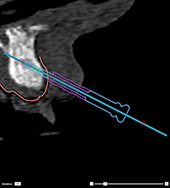

Correct inclination and depth of

anchor pins

To stabilize the surgical

template for implant insertion, anchor pins can be placed at strategic

positions. Their inclination

and depth are crucial.

The anchor pins can

also serve as lip retractors during surgery. Anchor pins spread too widely

within the arch could negatively affect mouth opening. A short-shaft version

of the anchor pin is available to mitigate this effect. Nevertheless,

the anchor pins should be planned so as to offer good access and should

not interfere with the implant sites.